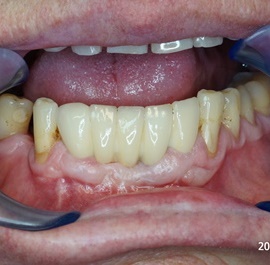

Pacjentka głosiła sie do naszego gabinetu do leczenia z osadzonym mikroimplantem w pozycji lewej dolnej dwójki. Siostrzany implant w pozycji prawej dolnej dwójki wypadł wcześniej, około 1,5 roku od implantacji. Odtworzono przedsionek i dziąsło rogowaciejące, osadzono dwa implanty, jednoczasowo z regeneracją kości. Dopiero na etapie ostatecznej rekonstrukcji protetycznej usunięto zachowany mikroimplant. To się nazywa motywacja do leczenia! Pacjentka przygotowywała sie na ślub prawnuczki :)

implanty stomatologiczne implanty stomatologiczne implanty stomatologiczne implanty stomatologiczne